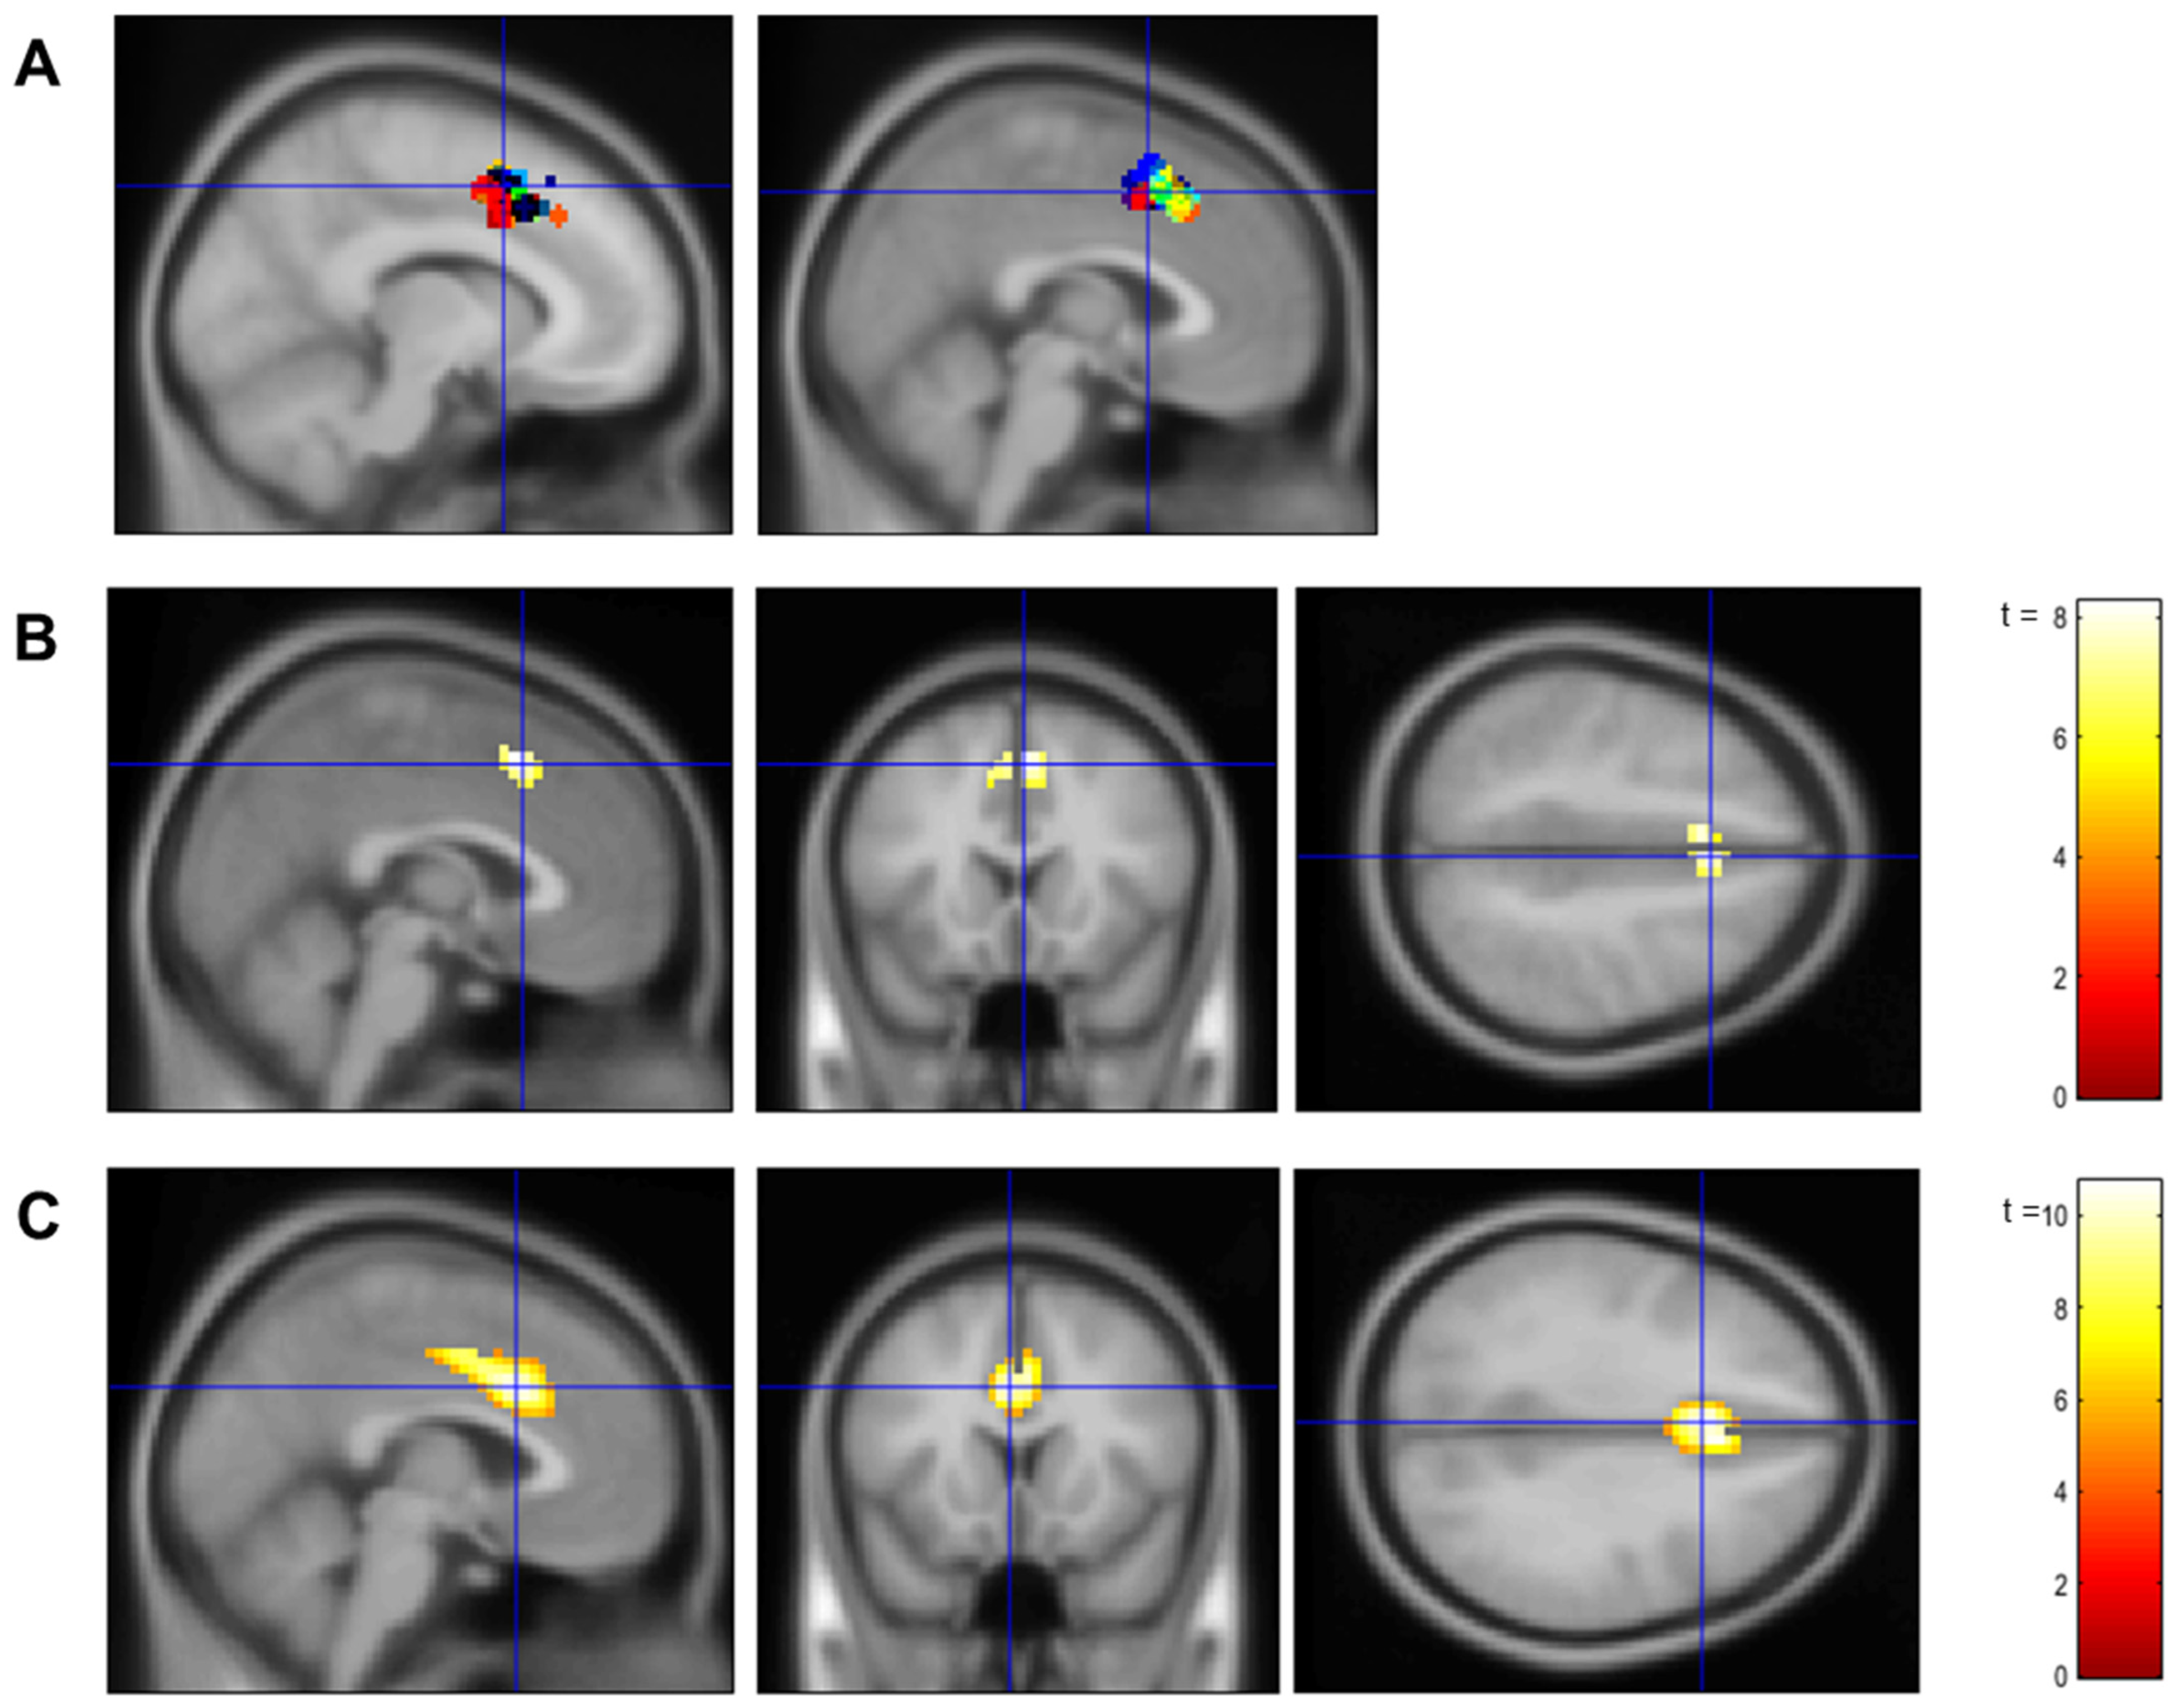

3.1. Confirmation of dACC Involvement in the Localizer Task and the Neurofeedback Training